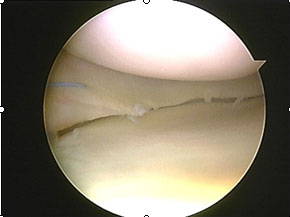

| Αρθροσκοπική εικόνα μηνίσκου 1 έτος μετά τη μεταμόσχευση βιολογικού ικριώματος |